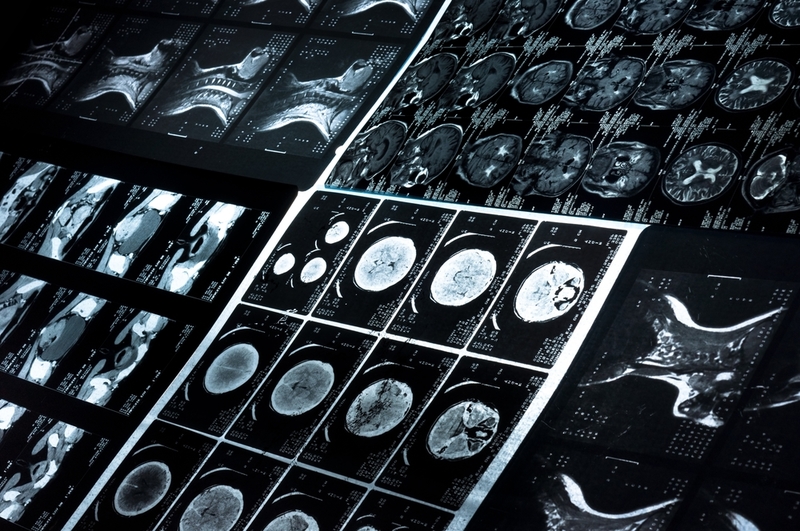

While it is quite common that head and neck cancers are often diagnosed late, new research conducted in Germany, shows that it is now possible to detect and diagnose the oral squamous cell carcinomas (OSCCs), most common head and neck cancers, at an earlier stage.

The researchers, who tested mechanical properties of OSCC cells, found them to be 'softer' than benign cells. Lead authors Josef Käs and Torsten W. Remmerbach said, "Early diagnosis and treatment of OSCCs is essential to enabling recovery. But in up to 60 percent of cases, the diagnosis is late because the growth has not been recognised, or has been mistaken as harmless."

The research team examined if cells' mechanical properties could be used as a marker for malignancy. As well as being softer than benign cells, the team saw that cancer cells exhibited a faster contraction than their benign counterparts when testing the relaxation behaviour after stress release.

Remmerbach added, "This new way of drawing distinction between malignant and benign cells could enable an early confirmation of cancer diagnoses, by testing cell samples of suspect oral lesions." The researchers used an optical stretcher to analyse the properties of the cells. Their experiments revealed that cells of primary OSCCs were deformed by 2.9 percent, rendering them softer than cells of the healthy mucosa, which were deformed only by 1.9 percent.